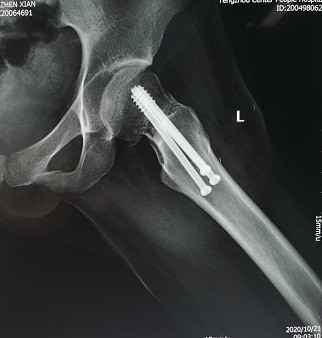

游离腓骨治疗股骨颈不愈合